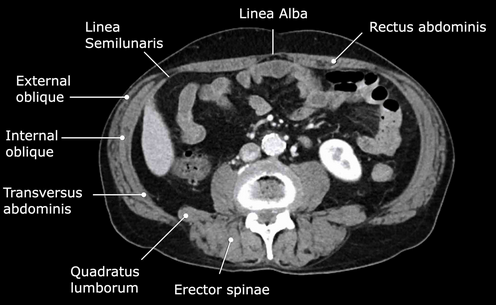

Normal abdominal CT scan. Normal anatomical structures of the abdominal walls (Courtesy Dr. V. Penopoulos)